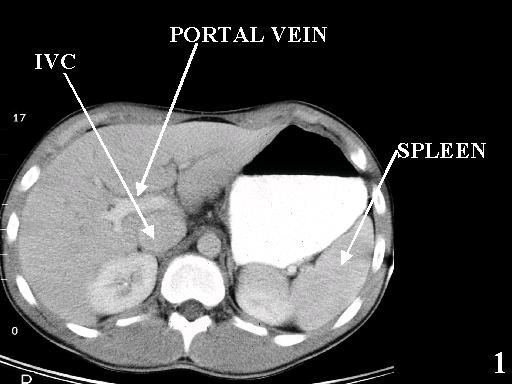

MS 190 CT 12